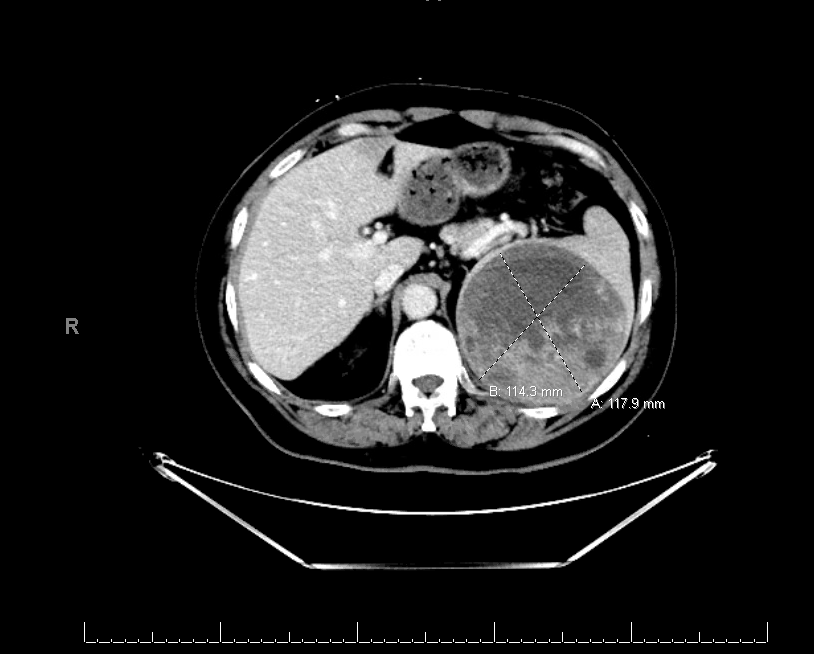

Case Presentation: A 65-year-old African American male with known comorbidities of Hypertension, coronary artery disease was brought to the hospital with a new-onset seizure. Upon presentation, vital signs were within normal limits. Physical examination noted left gaze preference, right hemiplegia, and aphasia. All labs including blood chemistries, complete blood counts, infectious workup, and urine drug screen were negative. Ct scan of the head showed left posterior mass. MRI brain showed 35 x 18 mm left parietal extra-axial enhancing mass concerning for meningioma. CT scans of chest/Abdomen/Pelvis were obtained for further metastatic workup. Interestingly his CT abdomen demonstrated a large complex partially necrotic splenic lesion measuring 12 x 12 x 12 cm with small areas of calcification. Of note, the patient did not report abdominal pain, nausea or vomiting. His abdominal examination was also unremarkable. The patient underwent left parietal craniotomy for tumor resection with histopathology showing atypical meningioma. Gastroenterology was consulted for further evaluation of the splenic mass. The patient then underwent an Endoscopic ultrasound with fine needle aspiration (FNA) which demonstrated an enlarged, mixed echogenic mass approximately 7 x 5 cm in size. Histopathology showed small lymphocytic lymphoma/Chronic lymphocytic leukemia. Due to the absence of adenopathy, cytopenia or B like symptoms, flow cytometry was also obtained which was consistent with CLL diagnosis. Given the patient was asymptomatic and there was no overt leukemia/lymphoma, the decision was made to do six monthly regular follow-ups to monitor for disease progression. Complete blood count, peripheral blood smear and repeat CT scan of the Abdomen showed stable disease at six months of follow-up.